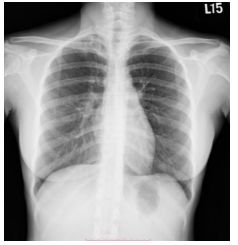

31.咳嗽 3 週